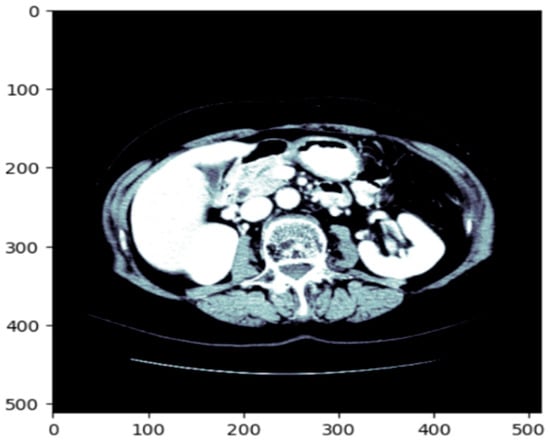

Before training the model, all volumetric CT images and corresponding masks were put through a structured preprocessing process. Initially, NIfTI (.nii) 3D volumes were loaded using the NiBabel library and reoriented to a standard axial orientation. Each volume was subsequently cut into individual 2D slices on the axial plane. Figure 3 shows a single axial slice of a CT scan after applying the windowing technique optimized for the liver. The windowing step improves the display of the liver and the surrounding tissue by adjusting the intensity range using the predetermined liver windowing parameters (width = 150, level = 30). The windowed bone colormap of an axial image can show the liver with respect to other structures in the abdomen by visually aiding segmentation. By adding the windowing, we can more clearly differentiate liver tissue from other organs, thus better supporting subsequent segments. Figure 4 depicts the unmodified input image (left), corresponding to the raw CT slice, and the windowed image (immediately left of the center), which improves the visibility of the liver by changing the range of intensities. The Mask (center-right) identifies the liver area, and the Liver and Mask Overlay (right) shows the liver area overlaid on the windowed image. This ensures more accurate segmentation and better visual perception. The slices were then resized to a fixed resolution of 128 × 128 × 3 pixels using bicubic interpolation for CT images and nearest-neighbor interpolation for masks to maintain categorical label correspondence. Additionally, histogram-based normalization and frequency-equalized scaling were optionally applied to enhance contrast uniformity among samples. CT images were saved in JPEG format for storage efficiency and compatibility with popular image processing pipelines, whereas binary masks were saved as PNG images containing a single grayscale channel.

Figure 3.

The original CT slice which enhances the contrast of the liver region to improve segmentation accuracy.